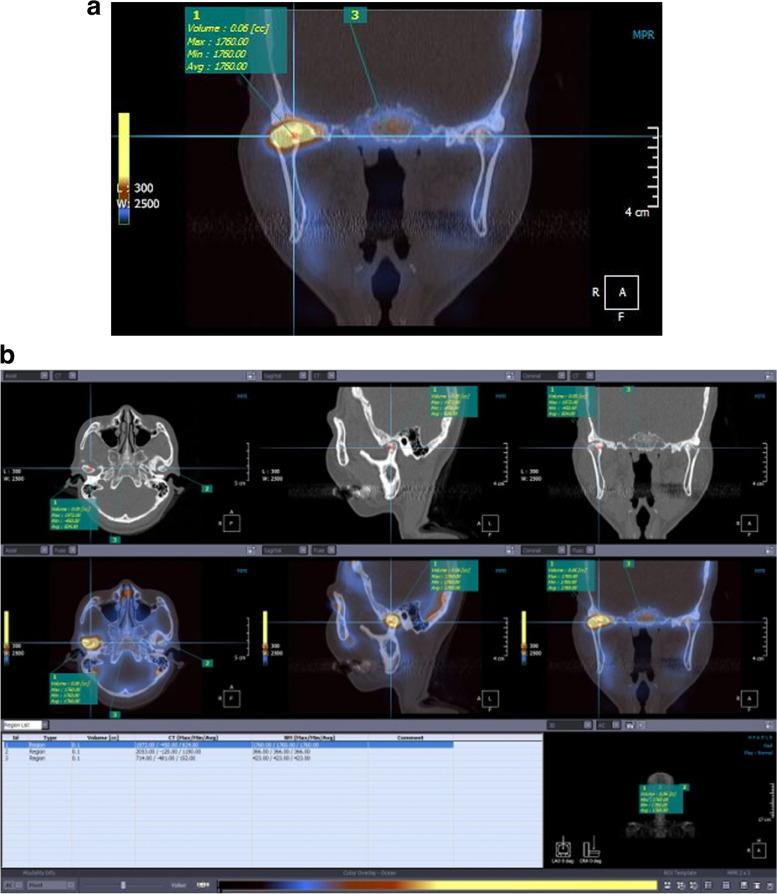

The primary objective of this study was to assess the clinical effectiveness of fused images obtained from single-photon emission computed tomography (SPECT) and facial computed tomography (CT) for evaluating degenerative changes in the mandibular condylar head. This assessment was accomplished by comparing the Technetium-99 m methylene diphosphonate (Tc-MDP) uptake ratio with the results of clinical and radiographic findings.

The study included 17 patients (3 males and 14 females) with suspected osteoarthritis of the mandibular condyle, totaling 34 temporomandibular joints (TMJs). Based on clinical and radiographic examinations, the TMJs were categorized into four groups: normal (group N), internal derangement (group ID), osteoarthritis (group OA), and osteoarthritis sequelae (group OA). For each patient, bone SPECT and facial CT scans were registered and reconstructed to create fused SPECT/CT images. The Tc-MDP uptake levels in the TMJs were statistically compared among the four groups.

The Tc-MDP uptake ratio showed a gradual increase in the order of the following: group N, group OA, group ID, and group OA. There was a significant difference observed among groups (p = 0.003), mainly driven by the disparity between group OA and both group N (p < 0.001) and group OA (p = 0.048).

Fused SPECT/CT image can be an effective tool for evaluating degenerative changes in the mandibular condylar head. The technique demonstrated the ability to differentiate between normal TMJs and those with internal derangement, osteoarthritis, or osteoarthritis sequelae. This approach holds promise as a valuable method in clinical assessments of TMJ degeneration.